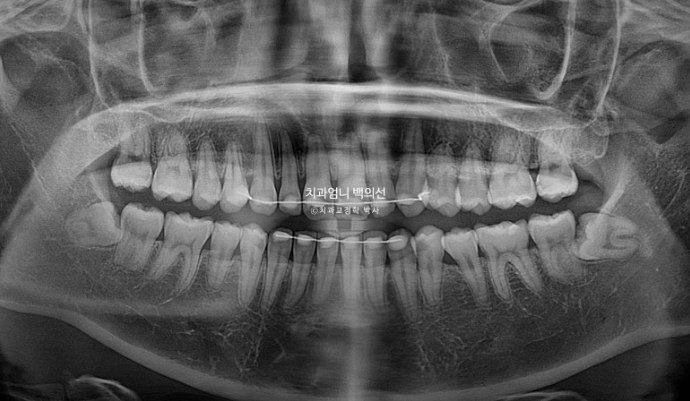

10개월의 치료기간 동안 치근흡수는 없으며 치근평행도는 양호합니다.

아래앞니과 위 앞니의 상당량의 함입이 눈에 띕니다. 위아래 앞니가 2mm씩 함입되었습니다.

덕분에 입술은 처음보다 좀 더 편하게 다물리게 되었습니다.